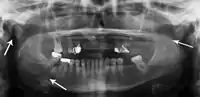

Panoramic radiograph of a simple mandible fracture of the right mandibular body, minimally displaced. Note that the teeth to the left of the fracture do not touch